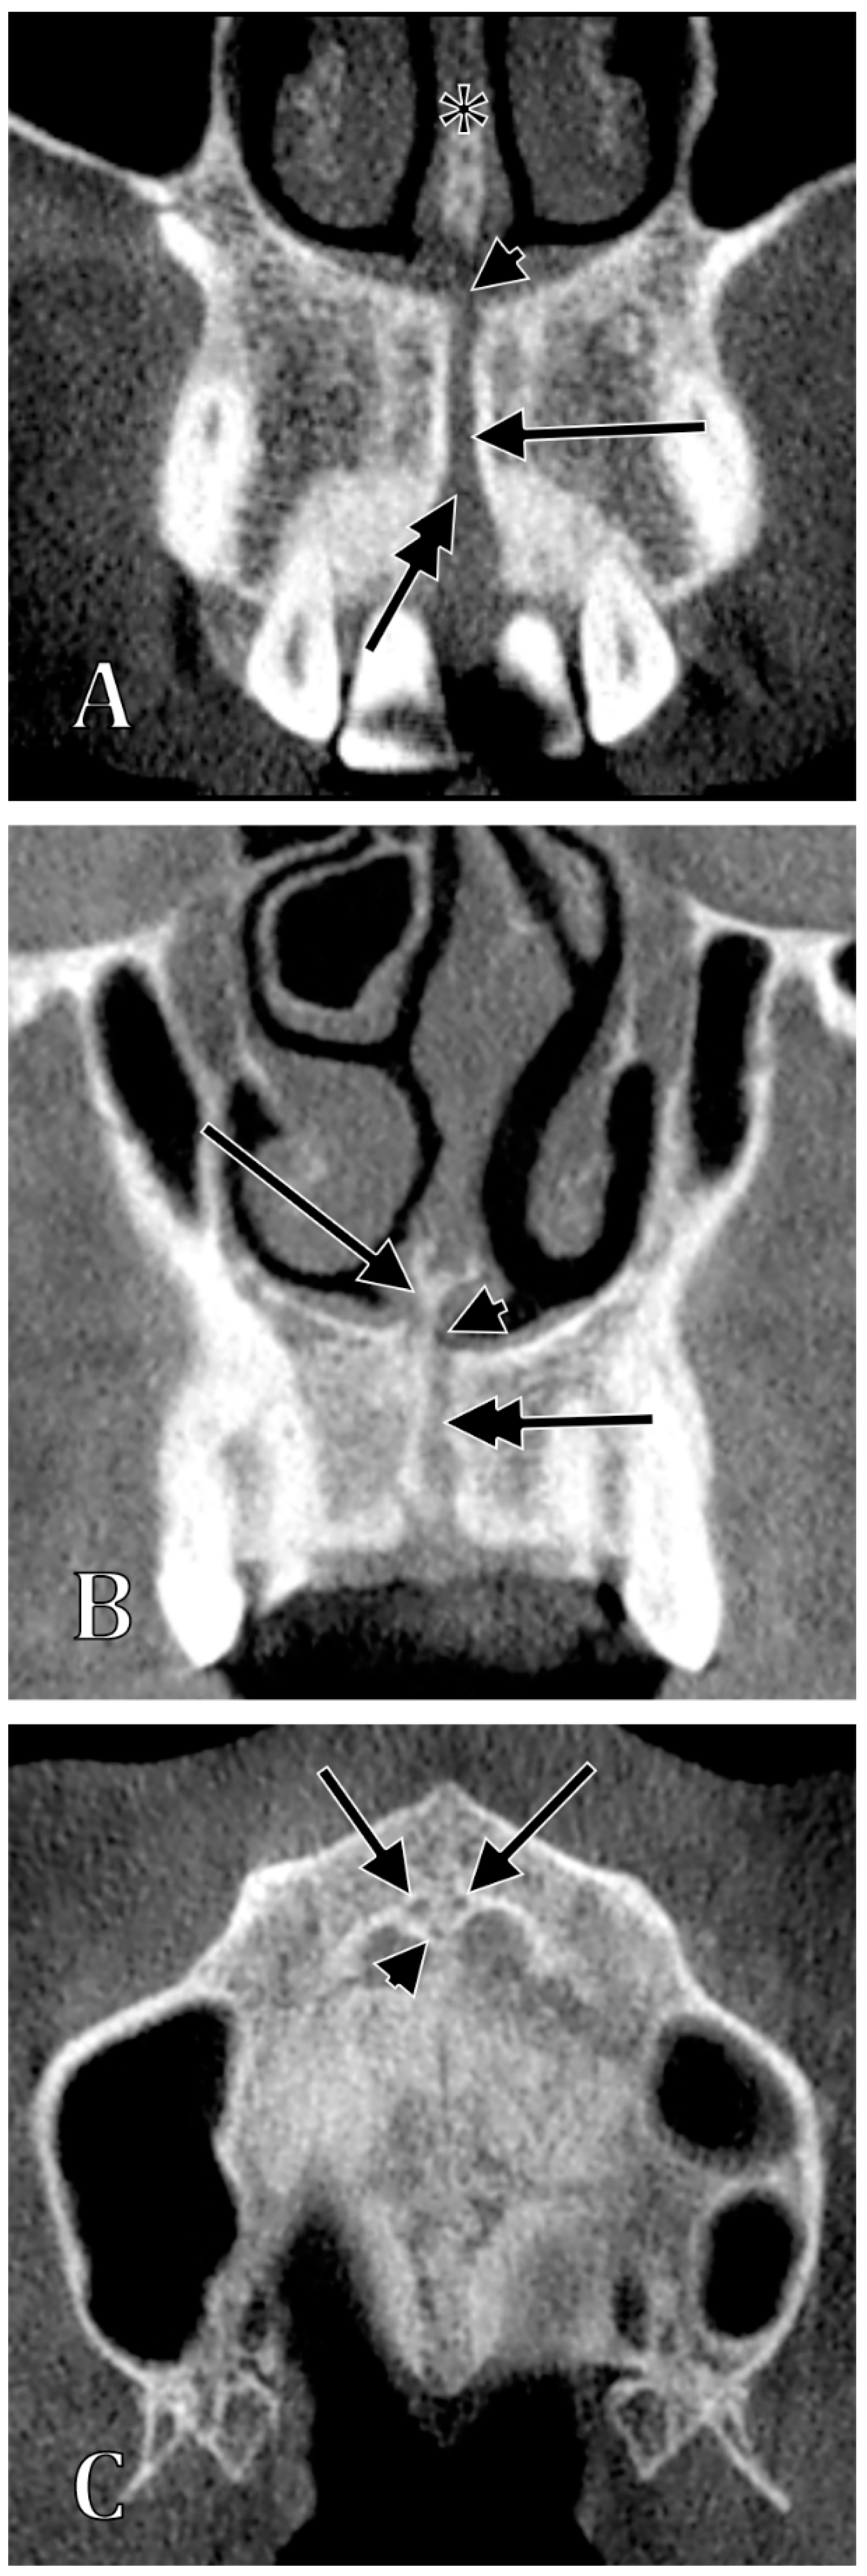

| Type of the NPC/IC | Characteristics of Types | Subtypes | Characteristics of Subtypes |

|---|---|---|---|

| I | NPC/IC present, 2 nasopalatine foramina | Ia | “Y”-shaped NPC/IC, with no secondary canaliculi |

| Ib | “Y”-shaped NPC/IC, with secondary canaliculi separated by a sagittal septum | ||

| Ic | “Y”-shaped NPC/IC, with unilateral secondary canaliculi separated by a coronal septum | ||

| Id | “Y”-shaped NPC/IC, with bilateral secondary canaliculi separated by a coronal septum | ||

| Ie | “Y”-shaped NPC/IC, with an added superiorly blind-ended median canal | ||

| If | parallel proper NPCs/ICs separated by septum | ||

| Ig | parallel proper NPCs/ICs unseparated by septum (NPC/IC unique, two nasopalatine foramina) | ||

| II | NPC/IC absent, 2 nasopalatine foramina | ||

| III | NPC/IC unique, 1 nasopalatine foramen | IIIa | unique median nasopalatine foramen, inferior to the nasomaxillary crest |

| IIIb | unique median nasopalatine foramen, on one side of the nasomaxillary crest | ||

| IV | NPC/IC present, 3 nasopalatine foramina, 1 median and 2 lateral | ||

| V | NPC/IC proper absent, absent nasopalatine foramina |